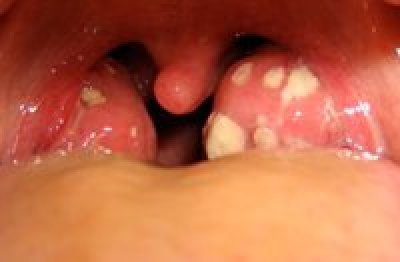

With prolonged conflict activity a flat growth (absorptive type) develops in the submucosa of the mouth. In the palate, salivary glands, tonsils, pharynx, and throat it can also take a cauliflower-shaped form (secretory type). If the papillae of the tongue that contain the taste buds are affected, the additional cells provide an enhanced sense of taste in order to be able to analyze (see sensory quality) the “morsel” (compare with hypersensitivity to taste related to the posterior third of the tongue).

Adenoids in the nasopharynx form as a result of a hanging conflict, that is, when the “scent morsel”-conflict cannot be resolved in time (compare with polyps in the paranasal sinuses). If the tonsils are affected, this causes tonsillar hypertrophy, or enlarged tonsils. Since the tonsils and the nasopharynx share the same brain relay, nasal polyps and enlarged tonsils often occur together.

HEALING PHASE: Following the conflict resolution (CL), fungi or mycobacteria such as TB bacteria remove the cells that are no longer needed.

In the mouth, the healing phase presents as canker sores (aphthous ulcers) on the inside of the lips or cheeks, on the palate or tongue, or in all areas of the mouth, depending on the perception of the conflict situation (compare with aphthous ulcers related to the mouth surface mucosa). Canker sores appear as round or oval white spots with an inflamed border. They can be quite painful. On the gums, the pus-filled pocket is called a “dental abscess” or gum abscess. The tuberculous discharge causes bad breath.